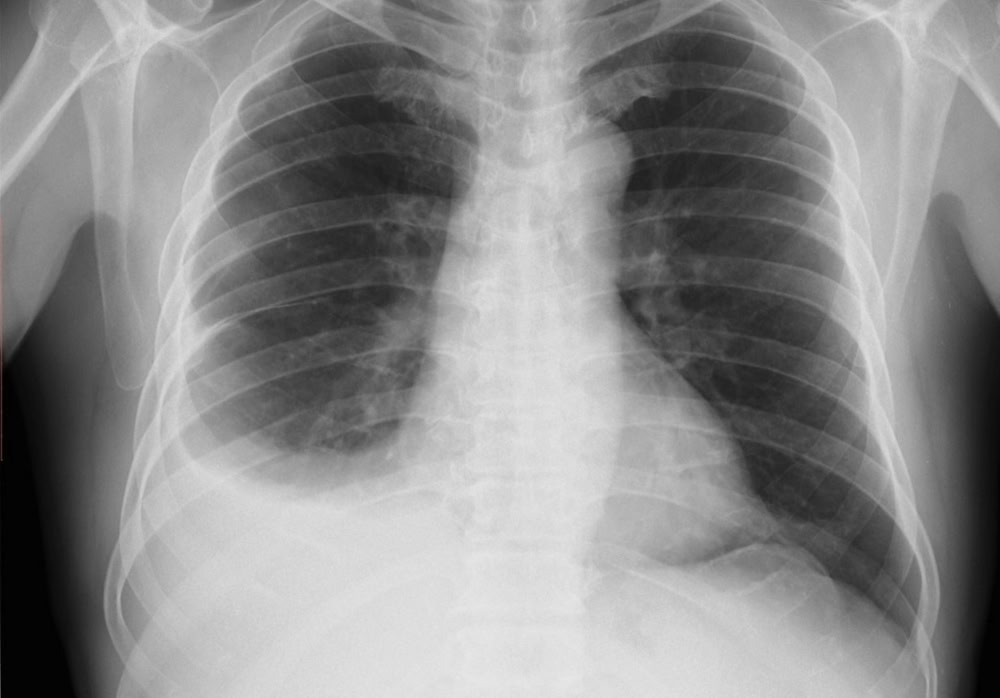

Первичной диагностикой занимается терапевт. Выявить состояние помогает простая рентгенография грудной клетки. Гораздо сложнее найти причину скопления жидкости. Для этого потребуется уже комплексное обследование организма. Лечение при малых объемах консервативное, большое поражение не обойдется без хирургического вмешательства.

Согласно клиническим рекомендациям, диагностический поиск включает в себя:

- рентгенографию легких;